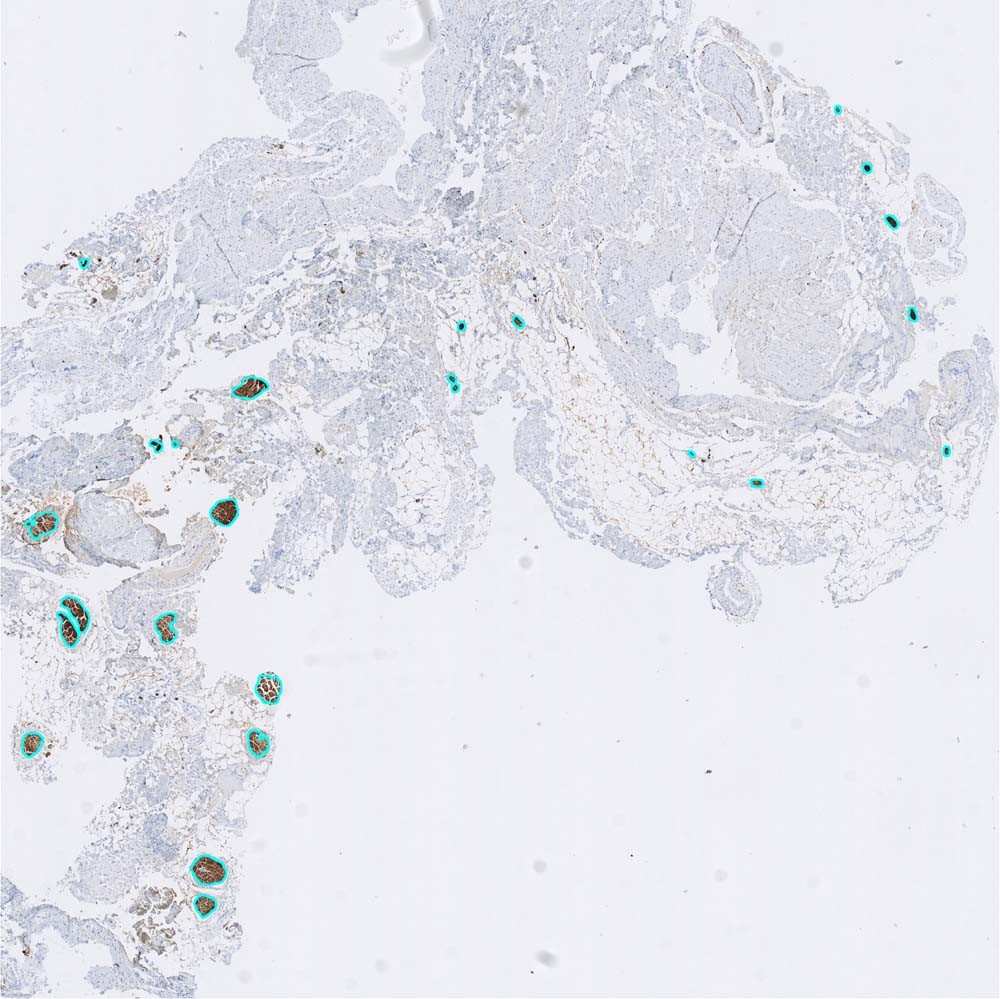

Figure 3

An illustration of quantitative analysis of the neural tissue proportion in a cross section of uterine branches of the inferior hypogastric plexus (×20). The indigo circles denote the neural tissue captured by the image segmentation method. A more detailed description is provided in Supplement 1.